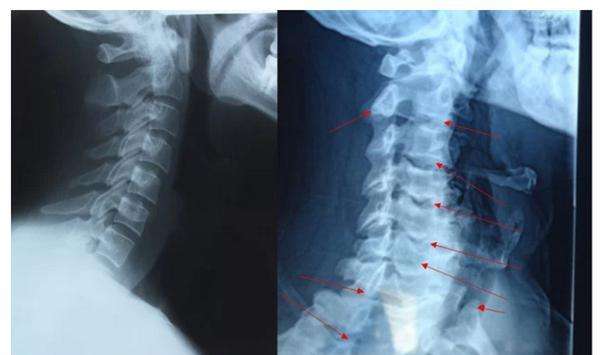

尤其是腰疼脖子疼膝盖疼,一拍片子,嘿!腰椎颈椎还真有骨刺,没准了,就是它了。再加上一些医术不精或别有用心的医生在旁边推波助澜的告诉患者,“你看,片子上有骨刺了,你的病就是这个骨刺引起的。但你不用担心,用了我的药就能让这骨刺消失。”

2、骨刺,只是X光片上看起来很尖,实际上并不是

是的,虽然X光片上看骨刺都是尖尖的,好像尖刀一样,但实际上,骨刺并不是尖的,而是钝的。

骨科医生在做手术时都会知道,那些在X光片上看起来尖尖的骨刺,在切开后会看到,其实骨刺表面包着一层圆润钝钝的软骨或结缔组织。只是这层圆润钝钝的软骨和结缔组织在X光片上不显示,只显示下面的骨头,所以尽管在片子上看骨刺好像是尖尖的,但是其表面其实是包着一层圆润的软骨的,并不会扎伤什么。

尽管大多数情况下骨刺并不会影响我们的生活工作,但是如果骨刺长的位置不好,或者“个头”长得过分了,如果碰巧压迫刺激到了旁边没多远的重要结构,比如:重要的血管、神经、脊髓等,这时骨刺就变的不那么美好。也只有这个时候才需要治疗,甚至手术。当然,这种情况其实非常非常少见。